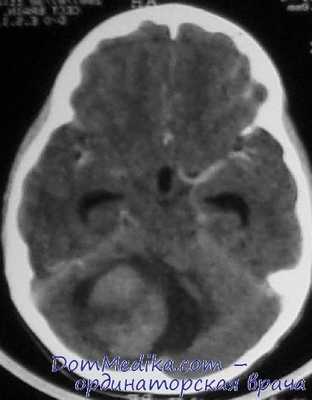

Диагностика болезни Лермитт-Дуклос производится посредством выявления характерных образований в мозжечке при помощи компьютерной и магнито-резонансной томографии. На КТ головного мозга при этом выявляется объемное гиперденсивное образование с размытыми и нечеткими краями, которое может быть расположено как на поверхности, так и в глубине мозжечка. МРТ головного мозга лучше всего производить с внутривенным контрастированием, поскольку именно такой метод позволит наилучшим образом изучить структуру и сосудистую сеть новообразования. При отсутствии технической возможности проведения данных исследований можно сделать рентгеновскую вентрикулографию - как правило, она показывает уменьшение или смещение четвертого желудочка и водопровода. Однако при незначительном размере ганглиоцитомы таких изменений может и не быть, поэтому вентрикулография не считается основным методом диагностики болезни Лермитт-Дуклос.